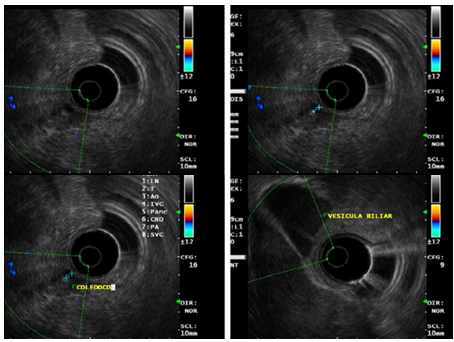

A 49-year-old male patient presents with a clinical picture of 11days of vomiting and diarrhea accompanied by abdominal pain, fever and jaundice during the last two days. Clinical history is positive for systemic hypertension, obesity and smoking. Physical exam showed tachycardia, jaundice and tenderness in the upper abdomen. Lab works showed: no leukocytosis, neutrophilia of 92%, liver enzymes of 115mU/ml and 179 mU/ml. Alkaline phosphatase of 129U/I, total bilirubin levels of 5.2mg/dl, Direct bilirubin of 3.3mg/dl, indirect bilirubin of 1.9 mg/dl, HDL of 250U/l, Amylase of 289U/dl, Lipase of 1900U/L, C-reactive protein of 24mg/dl, Electrolytes, renal function and coagulation were all normal. Hepatobiliary ultrasound showed a collapsed gallbladder (Figure 1). Bile system MRI showed thickened gallbladder wall, no gallstones, normal bile duct, dilated superior mesenteric vein with flow defect suggesting thrombosis (Figure 2). Contrast abdominal CT showed peri-appendicular inflammatory changes including a single fluid collection of 17x16mm, peripancreatic fluid and SMV flow defect-opacification indicating thrombosis (Figure 3). Normal Endoscopic ultrasound (Figure 4). The patient had findings suggesting systemic inflammatory response syndrome however in the absence of peritoneal irritation and ongoing pancreatitis, a conservative antibiotic treatment was chosen with ampicillin tazobactam, anticoagulation therapy with LMW heparin for 10days. The patient is discharged with a 21day antibiotic and 6month anticoagulation therapy. Appendectomy was programmed thereafter and the patient had full recovery.

Figure 4 Endoscopic pancreatobiliary ultrasound showing a 5mm common bile duct without any other echographic abnormalities.